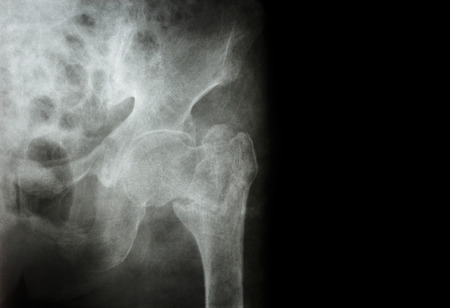

骨折により大量に出血した場合は、低血圧となってめまいや冷や汗、意識消失などの脳貧血症状があわられることもあります。 そのようなときはすぐに救急車を呼びましょう。 腫れている 骨折してから数時間後に、骨折部周辺が腫れてきます。. になって、10月の体罰事件が表面化です。 熊本市内のとある小学校にて、男性教諭が児童の足を蹴って骨折。 大怪我で未だに入院中だとか。 本当に信じられない指導、、、いや事件ですが、こ. 太ももには大腿骨という太い骨が一本通っています。 これの骨折が大腿骨骨折です。 大腿骨の上の方が折れると大腿骨近位部骨折、真ん中らへんが折れると大腿骨骨幹部骨折、下の方すなわち膝の近くで折れると大腿骨遠位部骨折と呼ばれます。 頻度としては、骨粗鬆症の高齢者が転倒するなどして、大腿骨近位部骨折となることが多いです。 症状としては骨折.

大腿骨骨折は、術後のリハビリが何より重要です。 大腿骨骨折が特に問題になるのは、どうしても力が入る部分だけに、 動かすと痛みも大きいことから、身体を動かすのが面倒になることです。 しかし、だからと言って高齢者が身体を動かさなくなれば、. なぜ高齢者は骨折しやすいのか? 高齢者に多い骨折の種類 高齢者に多い骨折は、大腿骨近位部骨折です。大腿骨とは太ももにある骨のことで、大腿部近位部骨折は太ももの付け根あたりで起こる骨折のことをいいます。 大腿部近位部骨折のなかでも、大腿骨頸部骨折と大腿骨転子部骨折が. 触ってみると分かりますが、ふとももには太い骨と筋肉が付いています。 特にヒトの場合は、上半身を支え、かつ歩行するのに使う重要な部位です。 ふとももの損傷は、筋肉などにも起こりますが、骨折する場合もあります。 もし骨にひびが入ったり折れたりすると、たいていの場合、痛みがひどくて歩くことができなくなります。 ふとももに入っている骨は.

なぜ高齢者は骨折しやすいのか? 高齢者に多い骨折の種類 高齢者に多い骨折は、大腿骨近位部骨折です。大腿骨とは太ももにある骨のことで、大腿部近位部骨折は太ももの付け根あたりで起こる骨折のことをいいます。 大腿部近位部骨折のなかでも、大腿骨頸部骨折と大腿骨転子部骨折が. 高齢者に多い4つの骨折とは 1 大腿骨近位部(だいたいこつきんいぶ)骨折 太ももの付け根の骨折で、転倒によって起こります。寝たきりになってしまう方も多く、社会問題となっています。 2 脊椎圧迫(せきついあっぱく)骨折 背骨の骨折です。. 「痛み分からせようと」教諭が小3の太もも蹴り骨折 熊本市教委が公表 /11/7 600 西日本新聞 社会面 長田 健吾.